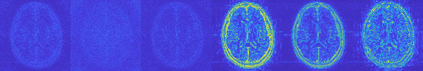

Magnetic Resonance Imaging (MRI) has excellent soft tissue contrast but is hindered by an inherently slow data acquisition process. Compressed sensing, which reconstructs sparse signals from incoherently sampled data, has been widely applied to accelerate MRI acquisitions. Compressed sensing MRI requires one or more model parameters to be tuned, which is usually done by hand, giving sub-optimal tuning in general. To address this issue, we build on previous work by the authors on the single-coil Variable Density Approximate Message Passing (VDAMP) algorithm, extending the framework to multiple receiver coils to propose the Parallel VDAMP (P-VDAMP) algorithm. For Bernoulli random variable density sampling, P-VDAMP obeys a "state evolution", where the intermediate per-iteration image estimate is distributed according to the ground truth corrupted by a zero-mean Gaussian vector with approximately known covariance. To our knowledge, P-VDAMP is the first algorithm for multi-coil MRI data that obeys a state evolution with accurately tracked parameters. We leverage state evolution to automatically tune sparse parameters on-the-fly with Stein's Unbiased Risk Estimate (SURE). P-VDAMP is evaluated on brain, knee and angiogram datasets and compared with four variants of the Fast Iterative Shrinkage-Thresholding algorithm (FISTA), including two tuning-free variants from the literature. The proposed method is found to have a similar reconstruction quality and time to convergence as FISTA with an optimally tuned sparse weighting and offers substantial robustness and reconstruction quality improvements over competing tuning-free methods.